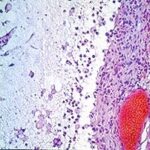

Atlas of skin histopathology

Mucus Retention =الأحتباس المخاطي